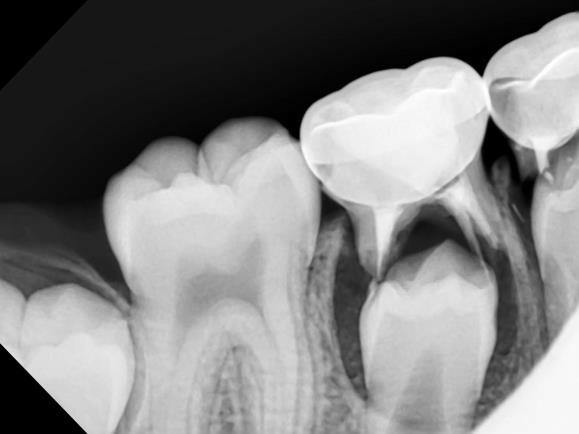

Dental sealants are thin, plastic coatings that seal over the narrow grooves found on the chewing surfaces of back teeth (molars and premolars).

When placed perfectly on these deep pits, sealants can prevent a significant amount of tooth decay (cavities) by protecting sensitive tooth surfaces from acid that causes cavities.

Sealants are not generally placed on baby teeth but on the tooth enamel of permanent teeth (“adult” teeth).

Dental sealants function much like sealing cracks in a driveway or on the sidewalk. The grooves in the chewing surfaces of back teeth are sealed so that food particles and bacteria will not settle within the fissures, causing cavities.

Application of sealants may be appropriate for some pediatric dental patients to prevent tooth decay in kids. However, they are not a substitute for brushing, flossing, and a healthy diet.